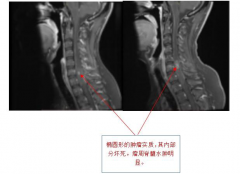

脊髓髓内肿瘤治疗方案附案例一

脊髓髓内肿瘤是起源于脊髓内组织的肿瘤,主要以室管膜瘤和星...